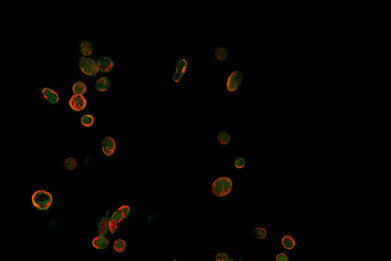

SEC61B (red) is seen in platelets (green) in diabetic mice. Credit: University of Sydney.

The study was led by Associate Professor Freda Passam of the University of Sydney Central Clinical School and Associate Professor Mark Larance of the University of Sydney School of Medical Sciences. The team discovered that a protein known as SEC61B was significantly elevated in the platelets of people with type 2 diabetes. The protein disrupted calcium balance inside platelets, which made them more prone to clump together and trigger clot formation.